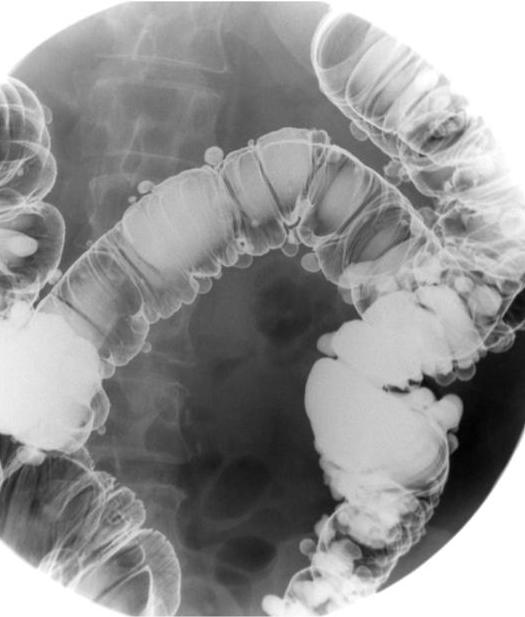

- Aspect des diverticules du colon

sigmoide sur le lavement baryte en

double de contrast . Image de reste de baryte dans

les diverticules en se voyaient si nette . |